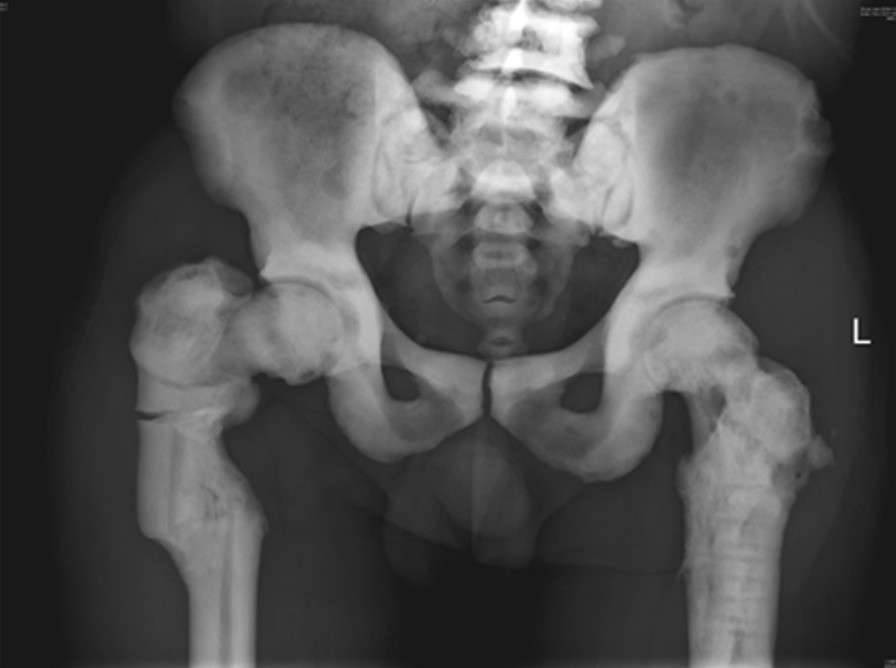

Radiograph taken three days before the first operation